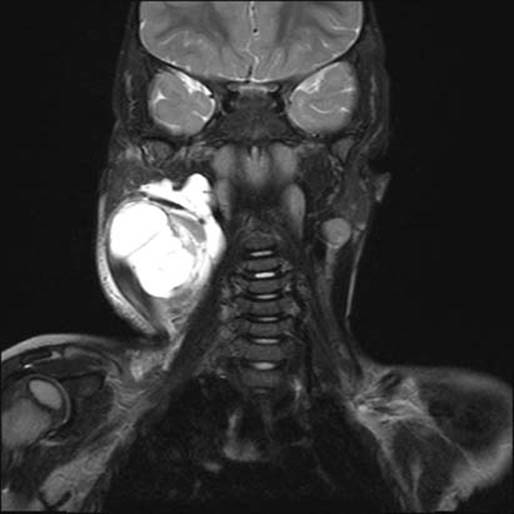

MRI with gadolinium is the best study for evaluating LMs and differentiating them from low-flow venous lesions. LMs are hypo- or isodense on T1-weighted images and hyperintense on T2-weighted images.13 Septations are clearly demarcated and margins are often distinguishable from adjacent tissue (Fig. 19.6). Recent infection or hemorrhage into the cyst appears as a heterogeneous fluid–fluid level. Chest radiographs can identify thoracic extension.

Figure 19.6 Coronal gadolinium-enhanced magnetic resonance image of right neck lymphatic malformation.